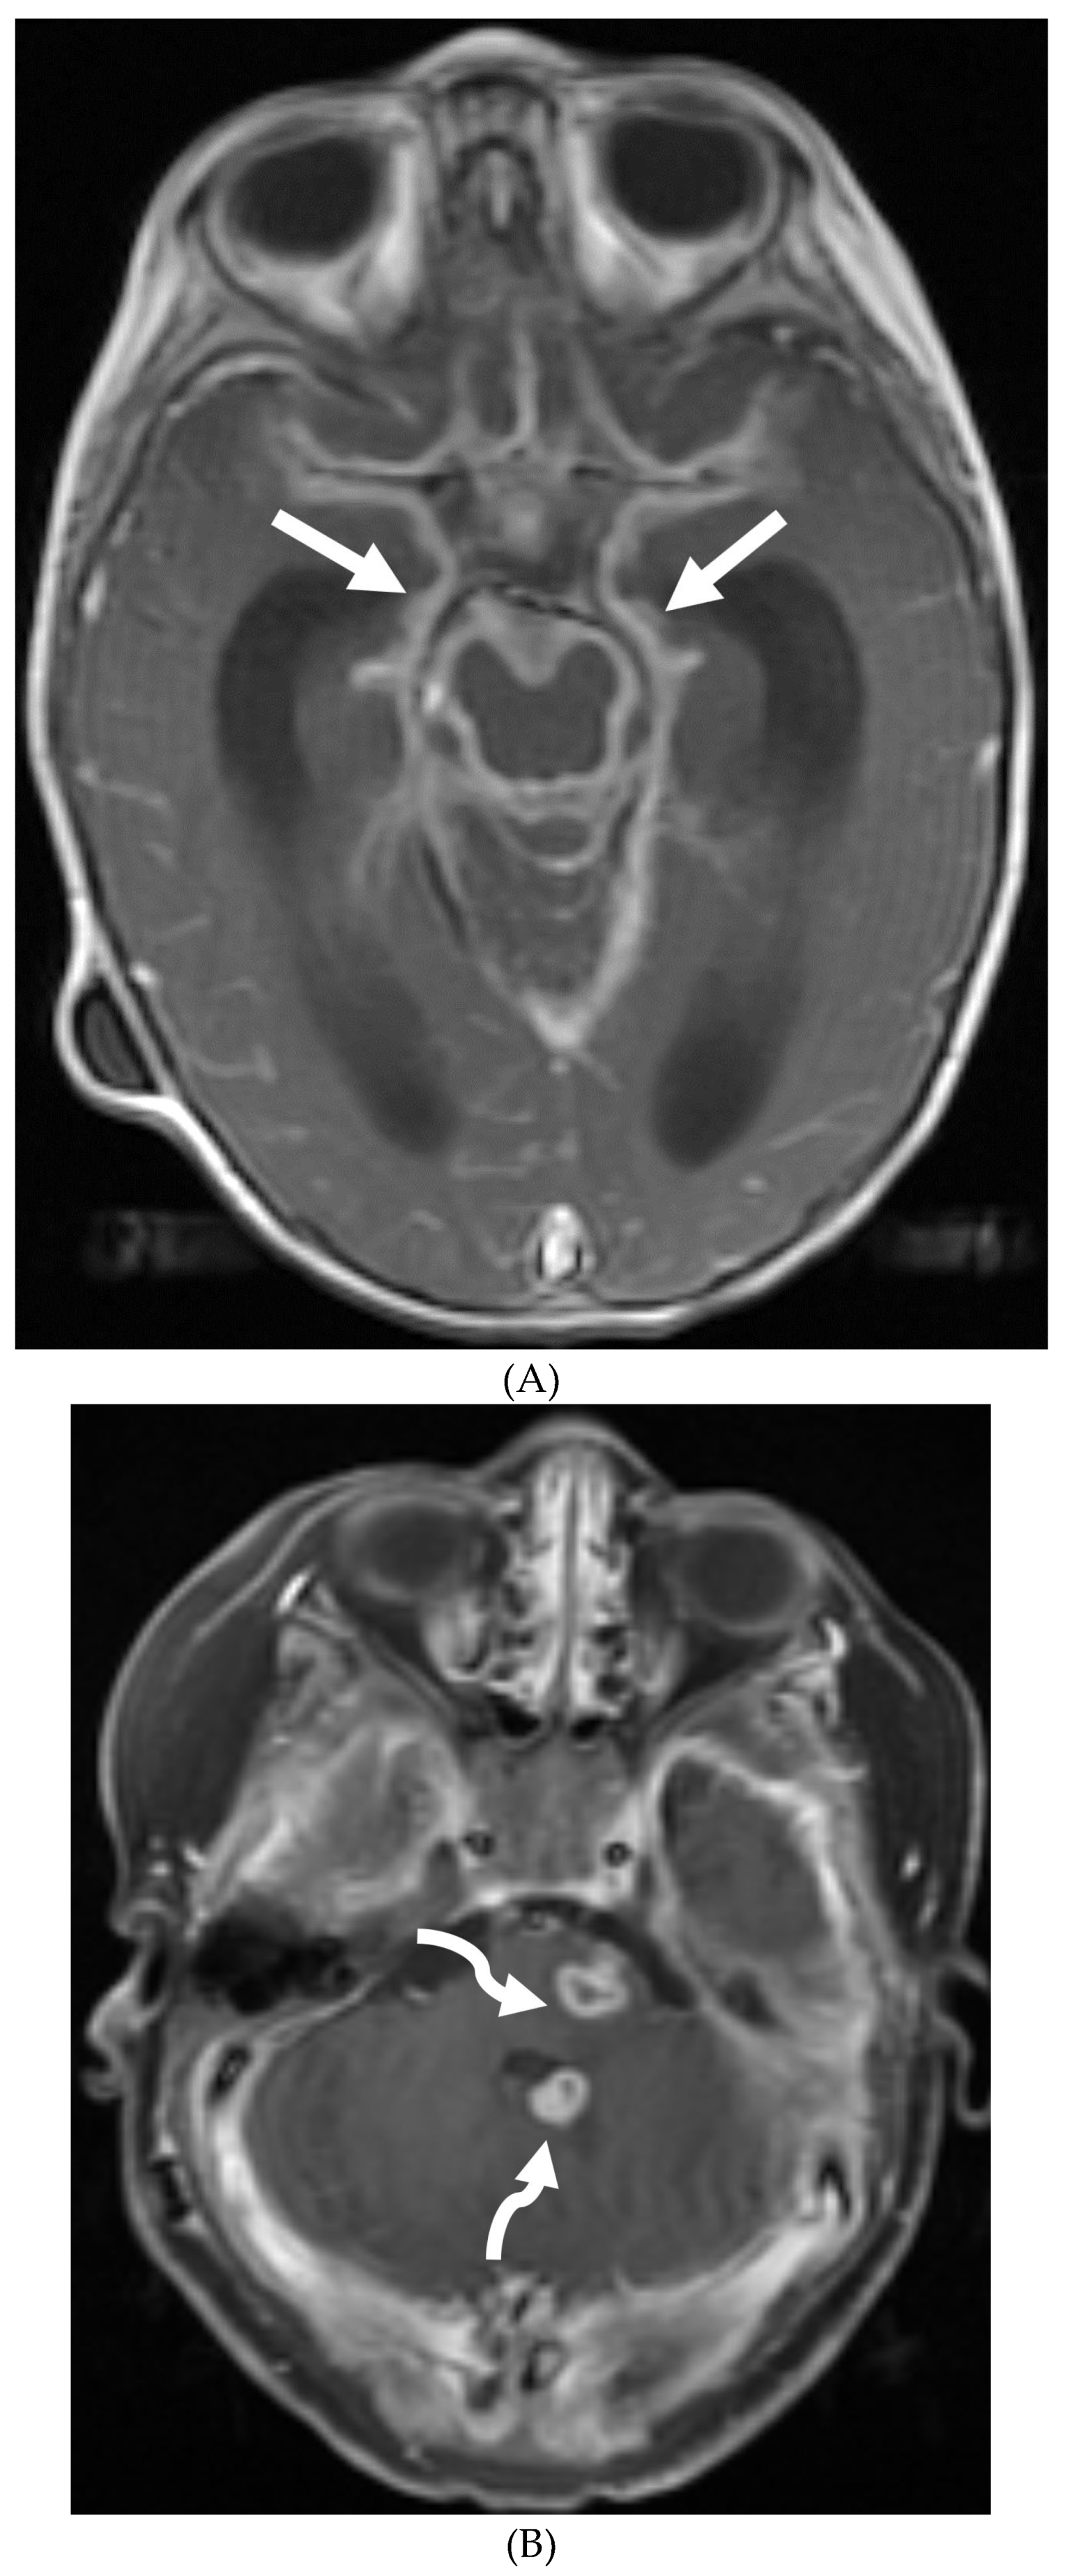

GUILLAIN BARRE SYNDROME

- Alkan O, Yildirim T, Tokmak N, Tan M. Spinal MRI findings of guillain-barré syndrome. J Radiol Case Rep. 2009;3(3):25-8. Epub 2009 Mar 1. PMID: 22470650; PMCID: PMC3303301. [CrossRef]

- Zuccoli G, Panigrahy A, Bailey A, Fitz C. Redefining the Guillain-Barré spectrum in children: neuroimaging findings of cranial nerve involvement. AJNR Am J Neuroradiol. 2011 Apr;32(4):639-42. Epub 2011 Feb 3. PMID: 21292802; PMCID: PMC7965877. [CrossRef]

- Yikilmaz A, Doganay S, Gumus H, Per H, Kumandas S, Coskun A. Magnetic resonance imaging of childhood Guillain-Barre syndrome. Childs Nerv Syst. 2010 Aug;26(8):1103-8. Epub 2010 Jun 17. PMID: 20556395. [CrossRef]

- Byun WM, Park WK, Park BH, Ahn SH, Hwang MS, Chang JC. Guillain-Barré syndrome: MR imaging findings of the spine in eight patients. Radiology. 1998 Jul;208(1):137-41. PMID: 9646804. [CrossRef]